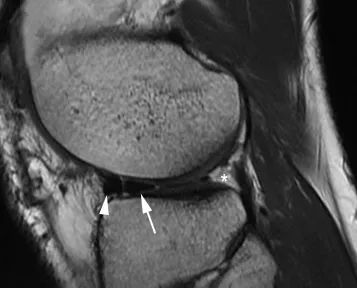

Наиболее частой находкой является прямая визуализация мигрирующих отломков в межмыщелковой области: ориентир «двойной задней крестообразной связки (ЗКС)» характерен при повреждении медиального мениска и интактности передней крестообразной связки.Вывихнутый сегмент выглядит как дугообразная гипоинтенсивная полоса, параллельная нормальной задней крестообразной связке, создавая вид «двойной ЗКС» (рис. 7).Избыточные грабельные рожки (размером более 6 мм) также могут свидетельствовать о наличии рукоятки ствола (рис. 8).В этом случае вывихнутый фрагмент мениска прикрепляется к здоровому переднему рогу.

Рисунок 8 Внешний вид переднего гигантского рога.Сагиттальный вид, взвешенный по плотности протонов.Передняя часть вывихнутого фрагмента (стрелка) прикрепляется к переднему углу мениска (стрелка).Обратите внимание, что задние углы не показаны (*).